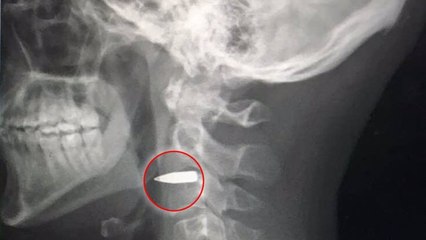

Laissé pour mort après avoir reçu une balle entre les yeux, ce corgi a miraculeusement survécu